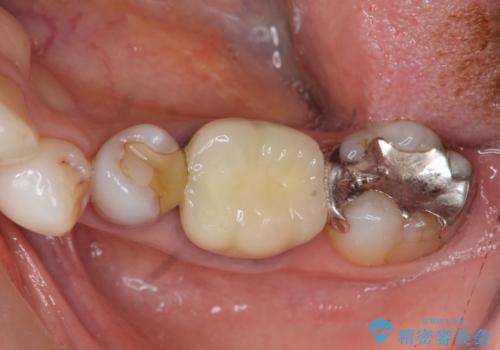

歯周外科で達成する、安定したクラウン周囲の歯肉環境

歯ぐきの腫れを改善する歯周外科手術を伴うセラミック治療